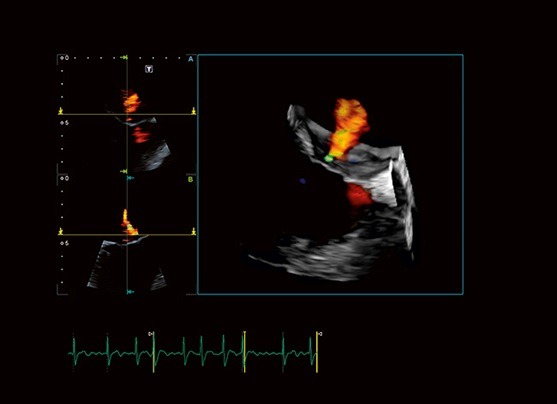

Aplio i900 تصویربرداری چهار بعدی قلب را به روال روزمره کلینیکی تبدیل می‌کند. پروب های تماماً آرایه ای شده، به طور خاصی کوچک و سبک هستند که آنها را ارگونومیک‌ تر و قابل دسترس‌تر می‌کند.

Aplio تصاویر Tissue Doppler و طیف های Pulsed Wave TDI با frame rate بالایی را به منظور زمان بندی دقیق فعالیت قلبی، به دو صورت بصری و کمّی، برای شما مهیا می‌کند.